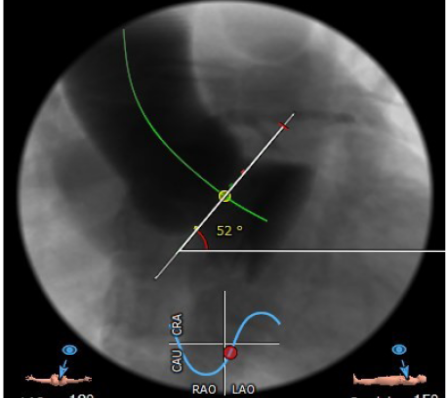

冠脉高度尚可。左冠高度:13.4,右冠高度:20.6。心脏角度52

3. 释放体位:结合瓣膜位置要求高,瓣膜下移风险大,故选择稍高1-2mm释放

5.其他风险:心脏角度偏横位心,升主增宽,增加过弓难度,置入输送器时可调整超硬导丝调整方向延小弯侧方向靠。心尖较薄注意超硬导丝塑形防止心尖穿孔。

在放射科,超声科和麻醉科的通力协作下,顺利完成了术前准备,术者团队在术中谨慎建立轨道,根据主动脉根部造影的结果选择合适的跨瓣体位。